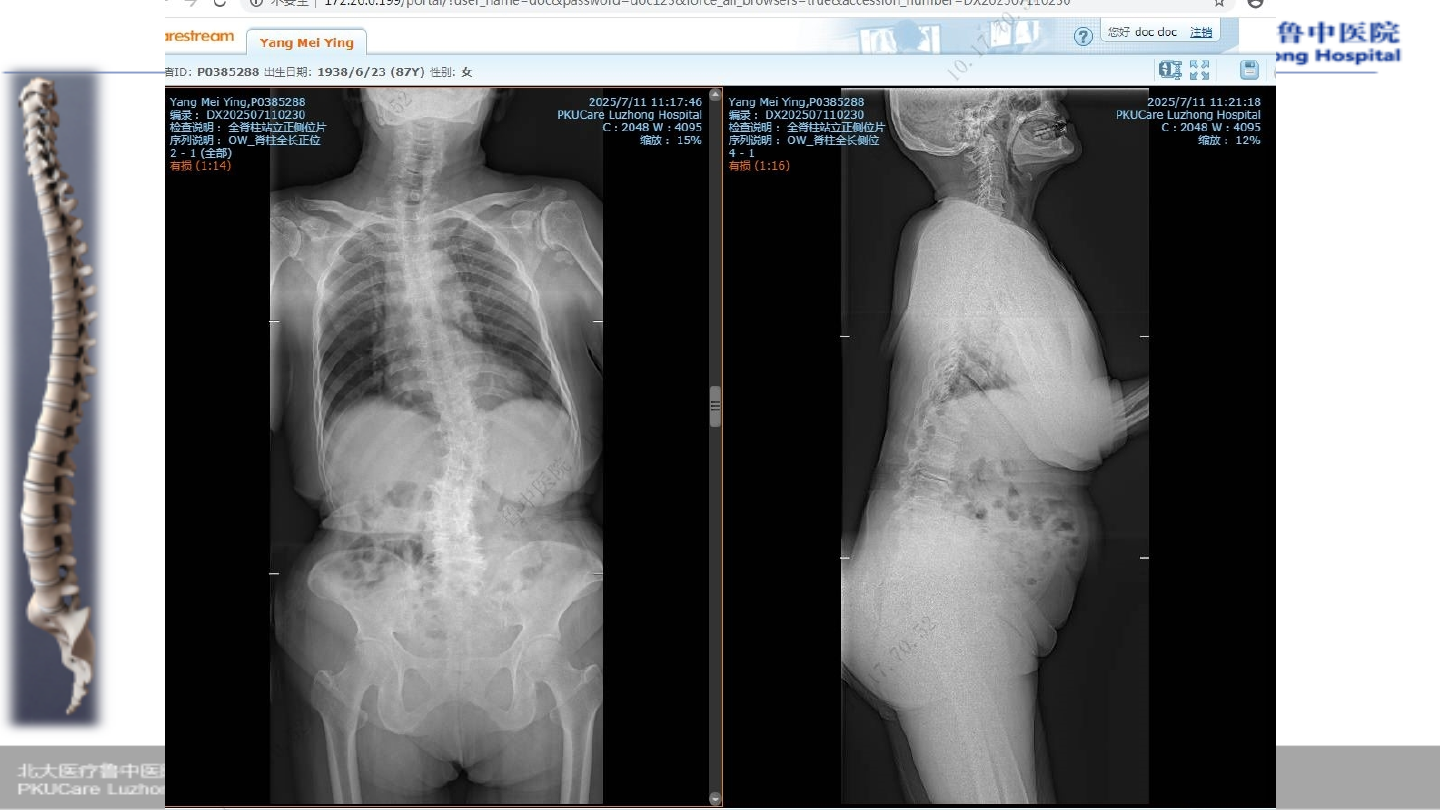

患者,杨某

,女性,

86

Ø

腰背部疼痛伴双下肢麻木疼痛

2

年,加重一周

腰背部疼

痛伴活动

受限

年前

症状加重

一周前

病例

3

术前

X-ray